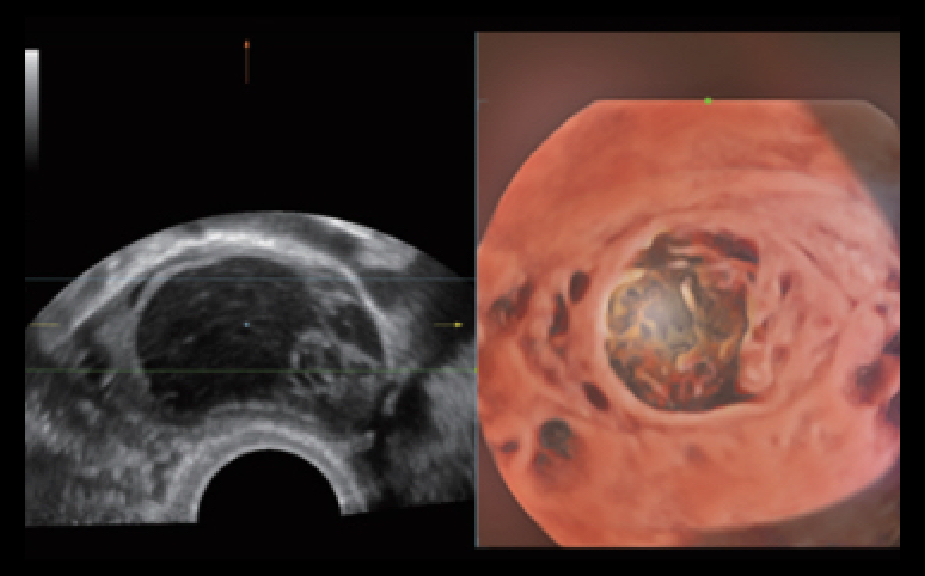

SoluciĂłn completa con tecnologĂa de ZST +

La plataforma ZST+?es una innovaciĂłn extraordinaria que representa toda una evoluciĂłn en el ĂĄmbito de la ecografĂa. Transforma las mĂ©tricas ecogrĂĄficas de la formaciĂłn de haces convencional al procesamiento basado en datos de canal. Supera la limitaciĂłn tradicional de tener que equilibrar entre resoluciĂłn espacial, resoluciĂłn temporal y uniformidad del tejido, con lo que ofrece una calidad de imagen excepcional para soluciones de producciĂłn de imĂĄgenes infinitas con mejoras continuas.